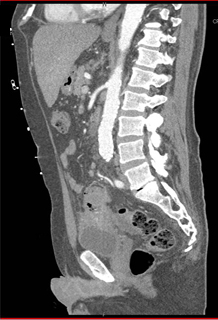

In this 70ish year old man the best diagnosis is

colon cancer

bladder cancer

diverticulitis

colovesicle fistulae